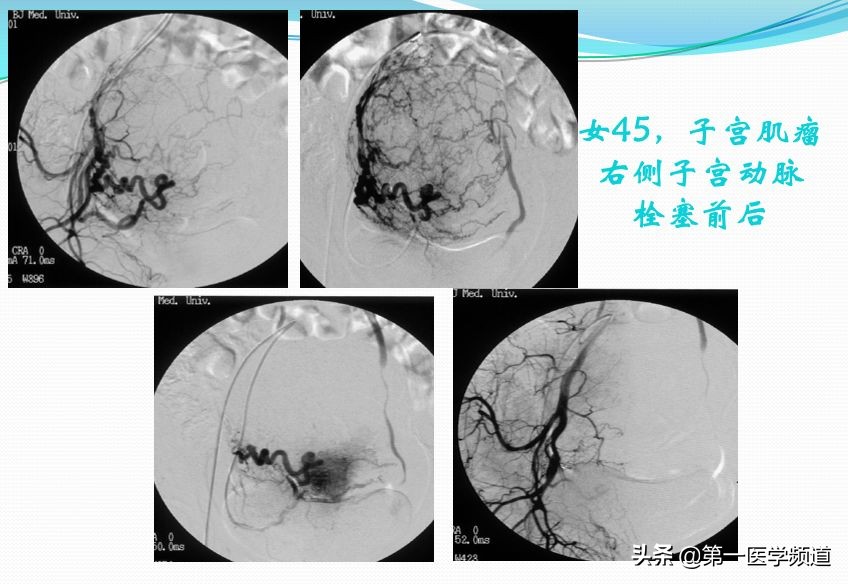

这也是一个非常典型的子宫肌瘤患者,45岁,右侧子宫动脉栓塞前后的对比图片。我们直接插管到子宫动脉以后,右侧子宫动脉做的造影,显示一个巨大的肌瘤。切除巨大的肌瘤以后,我们给她做栓塞治疗,栓塞治疗以后子宫肌瘤的动脉未见明确显示。

在磁共振上面,一个巨大的肿块——子宫肌瘤,大家可以明确看出子宫肌瘤栓塞术前术后的变化,子宫肌瘤明显缩小,部分引起坏死。